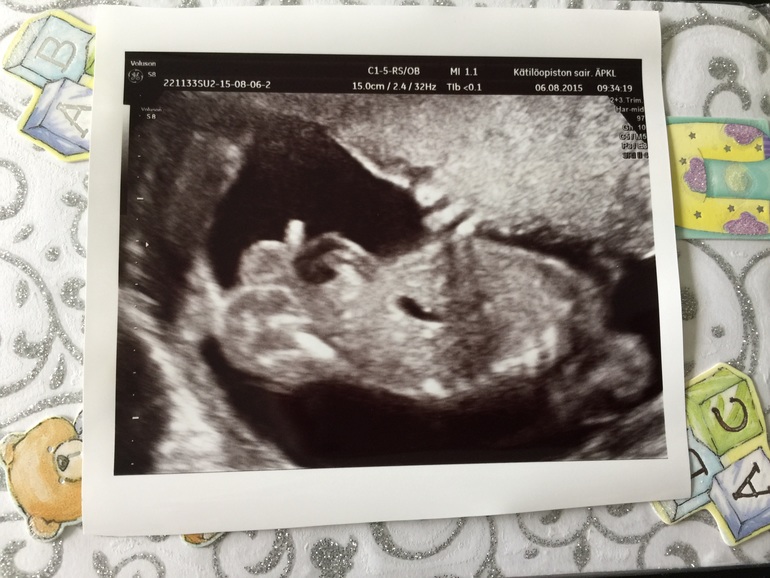

в итоге нашла кабинет)) Муж тоже ходил со мной, чему я безумно рада! Узистка попалась ну оооооочень приятная и хорошая женщина! Побольше бы таких!!!!!! Все рассказала, все показала, 500 фоток наделала и узи длилось 35 минут. Ложусь я значит на кушетку и тут мое сердце просто выпрыгивает из груди, думала в обморок рухнусь скоро. Гель, датчик, мои глаза нервно смотрели на манитор и тут она включает и я вижу свое чудо! Мой малыш! Как я сильно по нему скучала! Как я была рада его видеть!!! Брыкался, крутился, сосал пальчик и даже видела как глотал околоплодные воды. Это так прекрасно... На душе стало так тепло и хорошо.

Смотрю на монитор и до сих пор не понимаю что как во мне может расти человечек? Ну как? Он такой маленький и беззащитный и так хочется его скорее обнять, поцеловать и прижать к себе. Смотрю и понимаю как сильно его люблю!

Узистка все тщательно посмотрела, показала все органы и кости. Все у нас хорошо! Ну и то чего я ждала целых 20 недель... узнать пол малыша!

Вот фото: